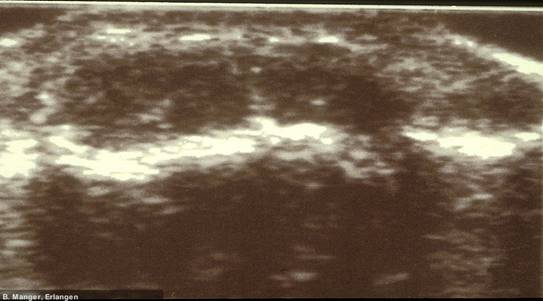

Calcinosis cutis (Doppler-Aufnahme) bei Dermatomyositis Calcinosis cutis (Doppler-Aufnahme) bei Dermatomyositis

Calcinosis cutis (Doppler-Aufnahme)